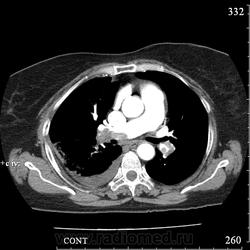

Еще один случай диагностики ТЭЛА методом КТ-ангиографии у женщины 59 лет. Основная клиническая жалоба - выраженная одышка. Определяется: полный дефект наполнения в системе правой ЛА (бифукация и нижнедолевая), неполный дефект наполнения в левой ЛА (нижнедолевая), пристеночные тромбы по задней стенке в области бифуркации обеих легочных артерий. Инфаркт (массивное кровоизлияние) нижней доли правого легкого. Правосторонний малый (120см3) гидроторакс. Несмотря на выраженные тромбы, поперечники легочных артерий - в пределах нормы.; на нативной (безконтрастной) КТ - тромбы не видны. Несмотря на почти полный дефект наполнения в левой нижнедолевой артерии, изменений в легочной ткани левого легкого нет. Также приводится топограмма, как вариант, приближенный к рутинной рентгенограмме